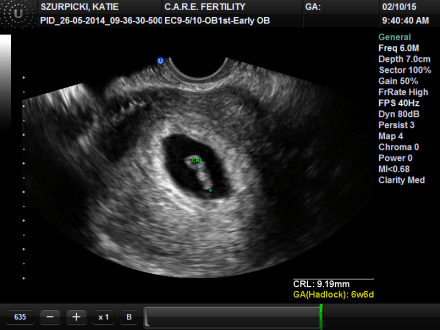

Both of my children were conceived via in vitro fertilization. This is not a secret and I have written about it before. What I have not written about is our Leo Lion’s conception. I have known what my beauties looked like from 3 days post conception. Amazing! This is our lion’s story.

I find it fascinating that from 6 days past creation he has exhibited very clear personality traits. We did not choose his name based on its meaning, but it is very apt. While IVF is considered a liberal choice, viewing and participating in the process of scientifically creating life has made me very conservative. I have known my child since conception, and I have seen his fierce determination since his cluster of embryonic cells forcefully left their shell. This is a gift and significantly cemented my view on when life begins. My child’s personality began at conception. I know this.